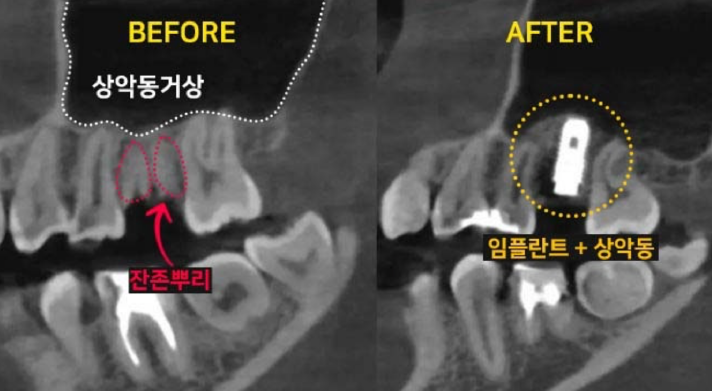

치아 손상으로 발치를 해야 할 때, '과연 바로 임플란트 시술이 가능할까?' 걱정하시는 분들이 많습니다. 이백점치과는 최신 의학 기술과 풍부한 임상 경험을 바탕으로 발치와 동시에 임플란트를 식립하는 것은 물론, 복잡한 케이스까지 성공적으로 진행하여 환자분들의 치료 기간과 불편함을 최소화하고 있습니다. ✨발치 동시 임플란트, 무엇이 다를까요? •일반적인 임플란트 식립: 치아를 발치한 후 잇몸과 뼈가 완전히 아물 때까지 약 3~4개월을 기다린 뒤 임플란트 를 식립합니다. 이후 임플란트와 뼈가 유착되는 데 3~4개월이 추가로 소요되며, 그 후에야 최종 보철물로 식사가 가능해집니다. 이 경우 치아가 없는 상태로 지내는 기간이 길어져 불편함을 느낄 수 있습니다. •이백점치과의 발치 동시 임플란트: 발치와 동시에 임플란트를 식립함으로써 치료 단계를 줄이고, 임플란트가 뼈와 유착되는 3~4개월 후에는 바로 최종 보철물(크라운)을 올려 즉시 식사가 가능합니다. 이를 통해 전체 치료 기간과 환자분의 불편감을 획기적으로 줄일 수 있습니다. CASE. 30대 여성 환자"이가 부러졌어요" ○ 환자분의 고민: 왼쪽 위 치아가 부러지고 염증이 생겨 임플란트를 희망하며 내원하셨습니다. ○ 진단: 파노라마와 CT 촬영 결과, 치아 뿌리만 남아있는 상태였고, 더 이상 치아를 살릴 수 없어 발치가 필요했습니다. 임플란트를 심을 수 있는 뼈가 5mm 정도로 부족하여, 일반적인 길이의 임플란트 식립을 위해 상악동거상술(뼈이식)이 동반되어야 하는 고난이도 케이스였습니다. ○ 치료 계획: 발치 후 즉시 임플란트 식립 & 상악동거상술 및 뼈이식 동시 진행  이백점치과의 정교한 발치 동시 임플란트 과정 과거에는 치아를 뽑고 3~4개월을 기다려야 임플란트 식립이 가능하다고 알려져 있었습니다. 하지만 이백점치과 는 다음과 같은 정교한 술식을 통해 발치와 동시에 임플란트 식립 및 뼈이식까지 가능하게 합니다. 1. 정확한 발치: 기존 뼈를 최대한 보존하며 잔존 치근과 치근단 염증을 완벽하게 제거합니다. 2. 이상적인 임플란트 식립: 환자분의 교합과 잔존 뼈를 고려하여 가장 이상적인 위치와 각도로 임플란트를 식립합니다. 3. 동시 뼈이식 및 상악동 거상술: 뼈가 부족한 부위에는 충분한 뼈이식을 진행하며, 특히 위턱 어금니 부위는 상악동 막을 안전하게 들어 올리는 상악동 거상술을 동시에 시행하여 임플란트가 단단하게 고정될 수 있는 기반을 마련합니다. 4. 깔끔한 잇몸 봉합: 빠르고 안정적인 치유를 위해 섬세하고 정확하게 잇몸을 봉합합니다.  빠른 회복과 뛰어난 예후: 믿을 수 있는 이백점치과 수술 직후부터 빠른 회복 과정을 보이는 것은 정확한 수술과 봉합 덕분입니다. 3개월 후 파노라마 사진에서도 상악동이 깨끗하고 뼈이식 부위가 자기 뼈로 잘 대체되고 있음을 확인할 수 있었습니다.  이처럼 발치 후에도 바로 임플란트 식립이 가능하며, 상악동 거상술과 뼈이식까지 동시에 진행될 수 있습니다. 이백점치과는 다양한 임상 경험을 바탕으로 고난이도 케이스도 성공적으로 이끌어내고 있으며, 수술 결과와 예후 로 환자분들께 신뢰를 증명하고 있습니다. |